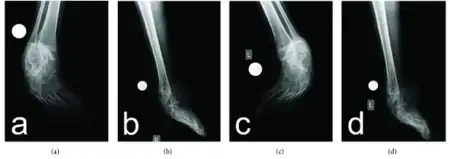

Hereditary motor and sensory neuropathy type I- a,c) anteroposterior b,d) lateral radiographs

Patients with hereditary motor and sensory neuropathies are diagnosed through a physical evaluation that looks for muscle atrophy, weakness, and sensory responses.[3] In addition to this, electromyography and motor nerve conduction tests can help clinicians decide what type of motor and sensory neuropathy it is and how severe the disease is. Final confirmation can come through genetic testing.